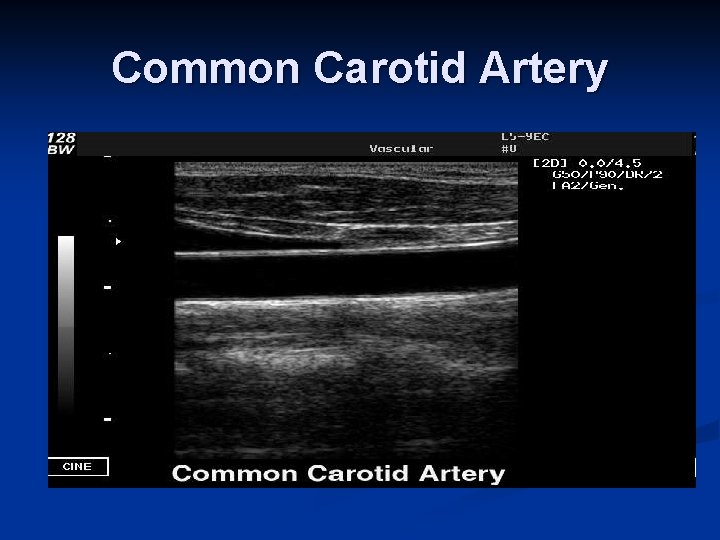

Common Carotid Artery